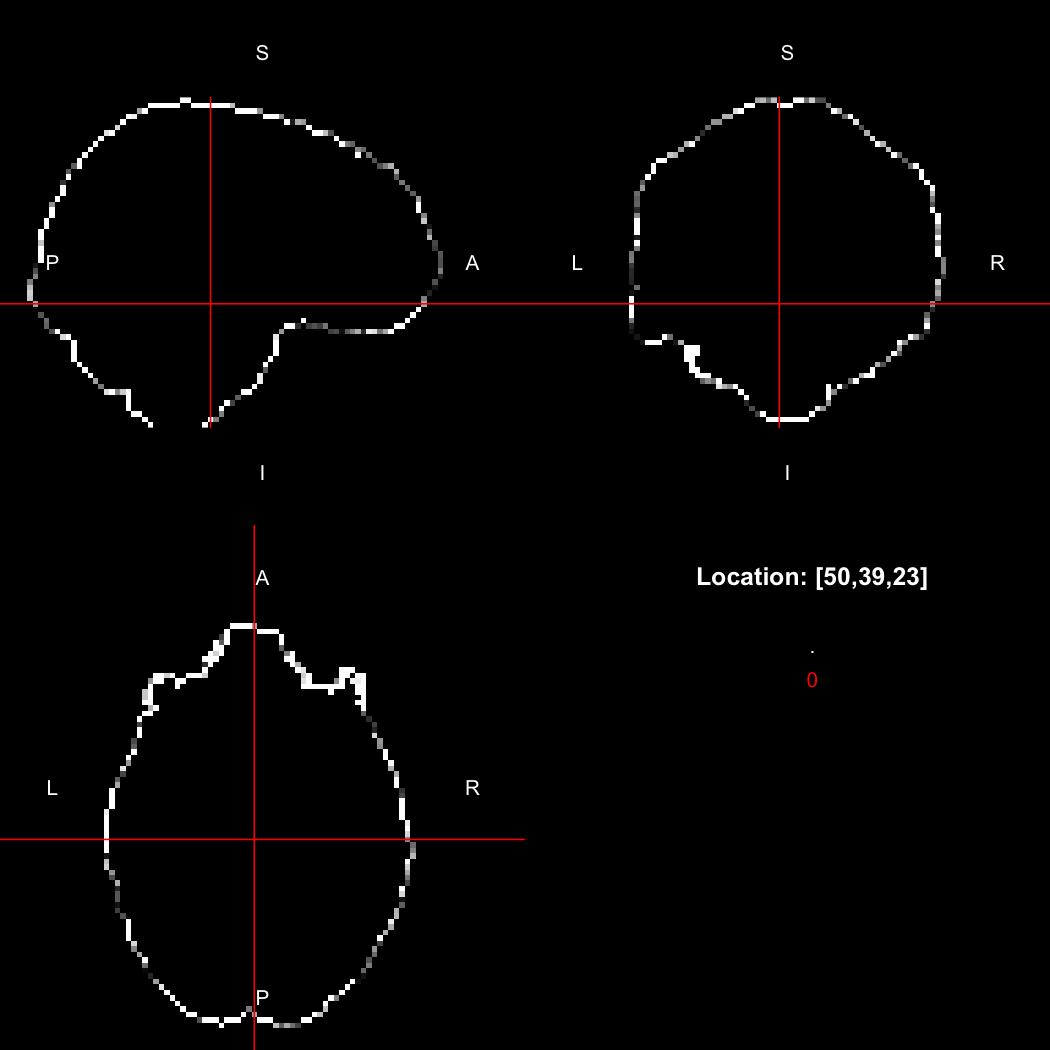

image %>% kernel_sphere(radius=3) %>% dilate() %>% subtract(image) %>% view()

## Setting window to (0, 60)

This example sets up a spherical kernel of radius 3 mm, dilates the image with it, and then subtracts the original image from the result to leave just the outer edge of the imaged object.